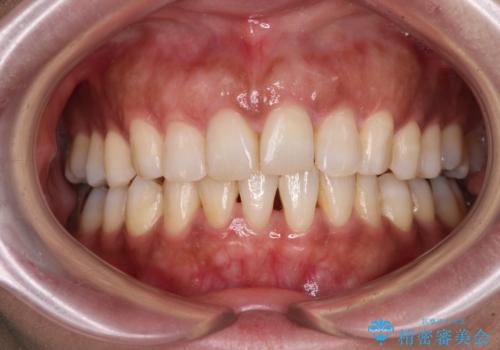

- デコボコと飛び出している前歯を気にして来院された患者様です。

歯列としてはインビザラインでもワイヤー矯正でも対応できるものでしたが、奥歯の咬み合わせを見た時に上顎がやや前方にあり、インビザライン単独では時間のかかってしまう可能性があるため、補助装置を治療当初に使用することで、インビザラインによる治療をスムーズに行えるように計画しました。